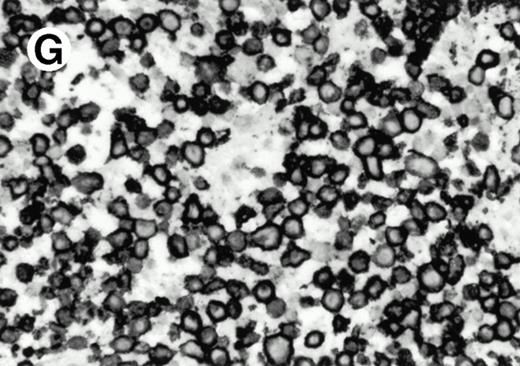

Both paraffin-embedded tissues and frozen sections (with or without heat antigen retrieval) were prepared for immunohistology as described in Materials and Methods. KPL1 stained numerous T cells in the T-zone (TZ) of a human tonsil (Fig 8A), but did not stain B cells in the mantle zone (M) or germinal center (GC) of the secondary follicles. Macrophages in the germinal center stained but follicular dendritic cells did not (Fig 8A). Just outside the germinal center, intense KPL1 staining of overlying plasma cells was observed. A high-power magnification (Fig 8B) shows this intense staining of plasma cells which surround the germinal centers. Subepithelial plasma cells also stained with KPL1 (data not shown), as did plasma cells around vessels in the skin (Fig 8C); these plasma cells costained with the plasma cell marker VS38 (Fig 8D). Thus, B cells located in germinal centers either lack the KPL1 epitope, or express it at levels which are not detected by these methods, whereas plasma cells in numerous sites express high levels. Similarly, four IL-6–dependent human myeloma cell lines expressed high levels of the KPL1 epitope (Diane Jelinek, personal communication, March 1997). Both cortical and medullary lymphocytes in the thymus stained with KPL1 (data not shown). Langerhans cells, bone marrow–derived antigen presenting cells which reside in the suprabasilar region of the epidermis, were also positive for KPL1 (Fig 8E). Langerhans cells in the tonsillar epithelium also stained with KPL1 (data not shown). Langerhans cells in soft tissue also stain with both KPL1 (Fig 8F) and CD1a (Fig 8G).

(E) Paraffin section of skin stained with KPL1. The Langerhans cells in epidermis and superficial dermis stain intensely in this example of Langerhans cell histiocytosis. The stained dendritic processes are apparent in the epidermis. (F) Langerhans cells in soft tissues also stain with KPL1. (G) Identification of Langerhans cells in (F) is confirmed by costaining with CD1a (immunoperoxidase with hematoxylin counterstain).